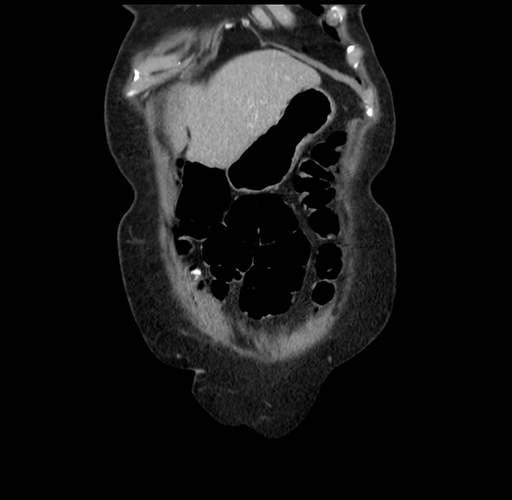

Pre-Chemo: Coronal Venous

Coronal Venous